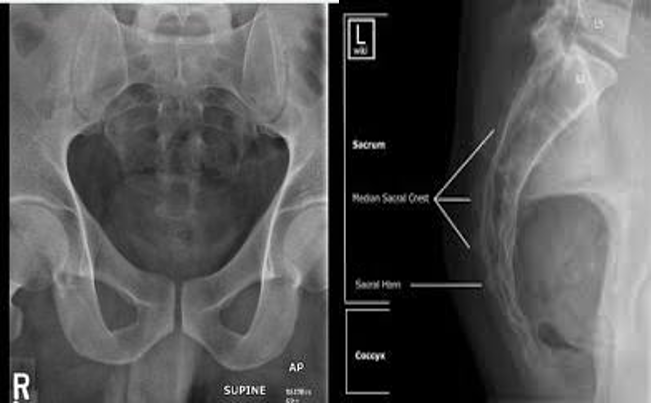

The Sacrum and coccyx